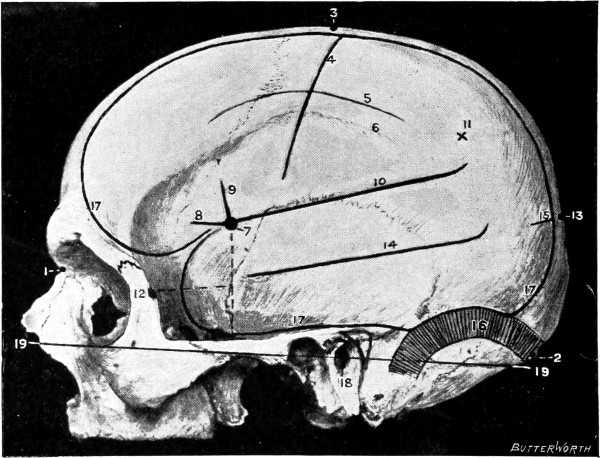

Fig. 2. Cranio-cerebral Topography. 1, 1, Reid’s base-line; 2, 2, A line parallel to the above at the level of the supra-orbital margin; 3, The middle meningeal artery; 4, The anterior branch; 5, 5, 5, The three sites for trephining; 6, The posterior branch; 7, The site for trephining; 8, The point for trephining to reach the descending horn of the lateral ventricle; 9, The lateral sinus; 10, The inion; 11, The mastoid process; 12, Macewen’s suprameatal triangle; 12a, The mastoid antrum; 12b, The facial nerve; 13, The suprameatal and supramastoid crests; 14, 14, The temporal crest; 15, The temporal fossa; 16, The external angular frontal process; 17, The tendo-oculi attachment; 18, The lachrymal groove. (Reproduced, by the permission of Mr. H. K. Lewis, from the author’s work on ‘Landmarks and Surface-markings’.)

Larger illustration (top)

Larger illustration (bottom)